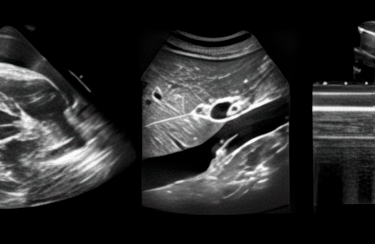

Systematic, quick and confident FAST, RUSH and FATE protocols.

The simple mindset to quickly acquire every standard echo view without having to think.

Speed reading cardiac wall motion abnormalities without AI: The simple process to take a year off your expertise curve.

The usual and precise means to evaluate Central Venous Pressure: more than just IVC respiratory variation.